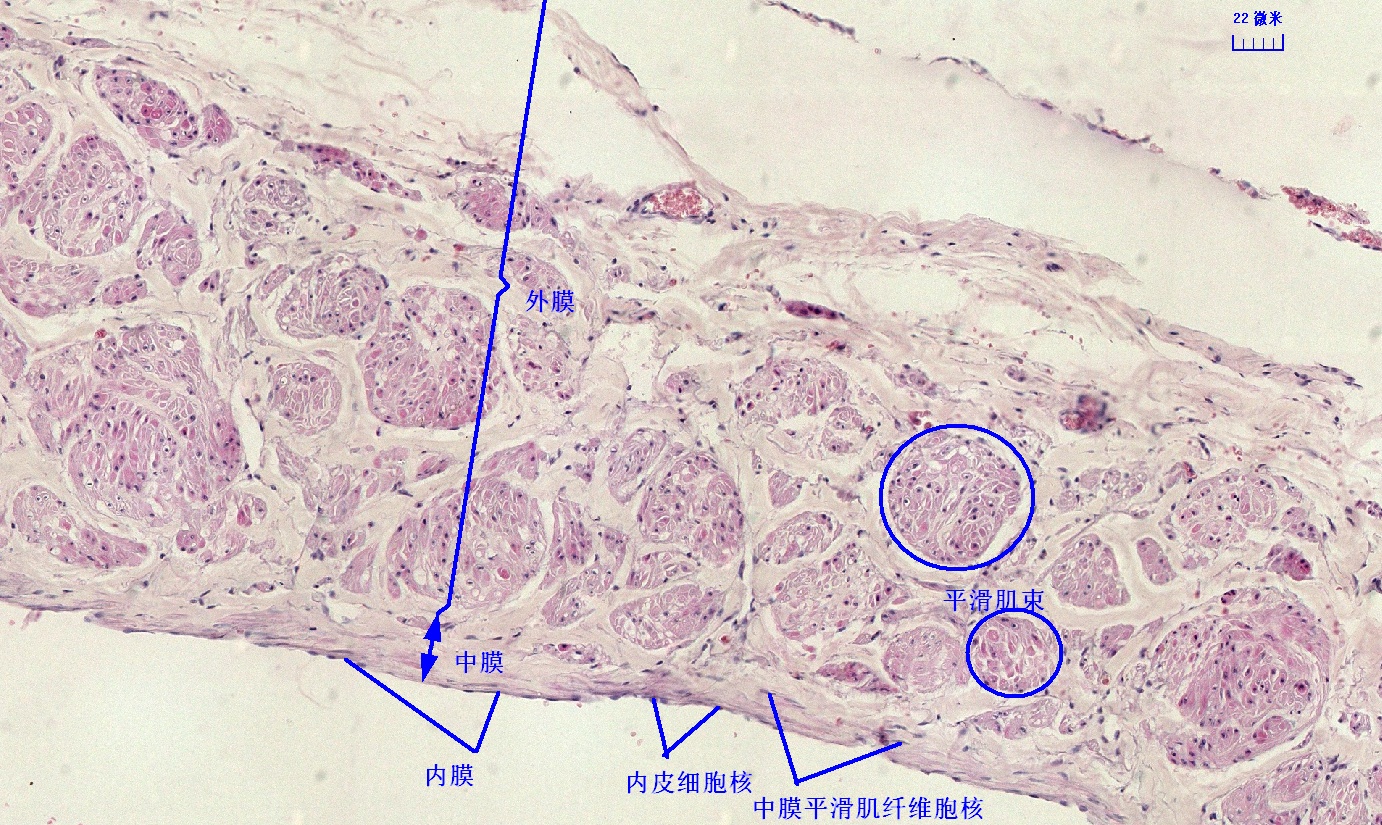

6 第六单元 循环系统

6.1 循环系统切片库

6.2 循环系统微课

6.3 循环系统课件